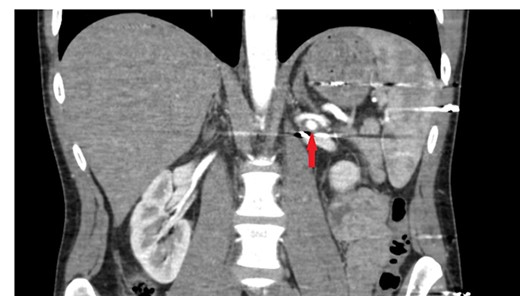

The patient was re-evaluated with CTA 3 weeks after discharge. Endovascular intervention was planned after observing that the left RAP was enlarged to 6 mm (Fig. 2). A renal angiogram was performed. After selectively catheterizing the left renal artery, a 6 × 3 mm filling extending inferiorly in the middle part of the left renal artery compatible with RAP was observed (Fig. 3). Following catheterization of the left renal artery with a long sheath, the lesion segment was passed with guide wire-catheter manipulations. Subsequently, a 6 × 22 mm covered stent (Advanta V12 Balloon Expandable Covered Stent, AMC, USA) was placed to include the RAP neck, and full expansion of the balloon and stent was achieved (Fig. 3). The control images revealed that the RAP was excluded from circulation, and the stent was patent. No embolism or bleeding was observed in the distal renal artery branches.

Tomographic angiography image of the enlarged renal pseudoaneurysm and the retained bullet core.